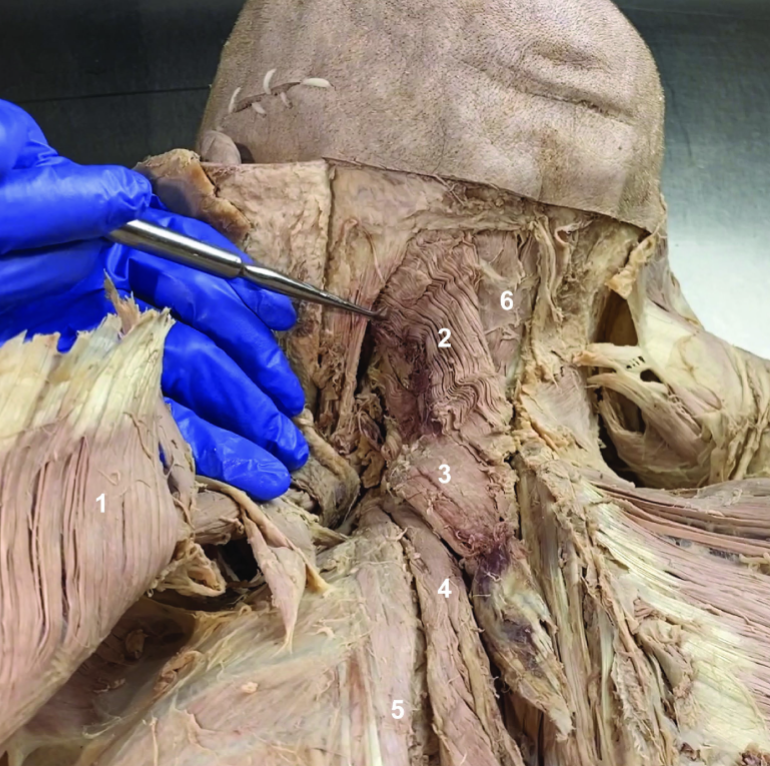

ID structure

Spinal accessory n. (CN XI)

ID structure

Transverse cervical a.

ID structure

Levator scapulae

ID structure

Rhomboid minor

ID structure

Rhomboid major

ID structure

Rhomboids (reflected)

ID structure

Splenius capitis

ID structure

Splenius cervicis

ID structure

Longissimus

ID structure

Iliocostalis

ID structure

Semispinalis capitis